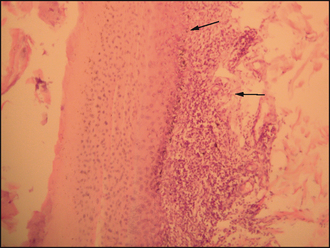

As the dew claws were affected in this case, the third phalanx of one was surgically removed and submitted for histology. Post-surgery analgesia with meloxicam was prescribed. Histology revealed interface dermatitis, with hydropic changes of the basal epithelium and mainly lymphocytes and plasma cells targeting the dermoepidermal junction (Fig. 56.3). These findings supported a diagnosis of immune-mediated lupoid onychitis. Acantholysis and clefting, histological signs of pemphigus, pemphigoid and epidermolysis bullosa, were not evident. There was evidence of mild perivascular dermatitis, but the histological signs associated with vasculitis were absent.

image

Figure 56.3 Interface dermatitis (arrows) demonstrated on histology.